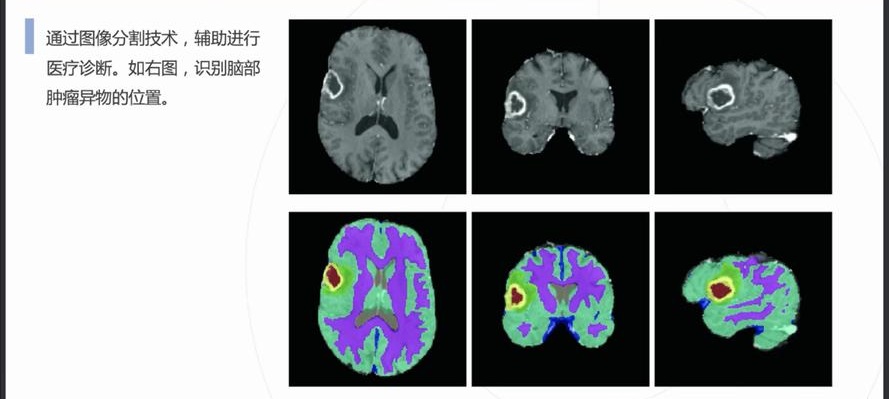

自動病灶檢測:借助計算機視覺和人工智能算法,CCD視覺檢測設備能夠自動識別醫學影像中的病灶區域,如腫瘤、炎症、骨折等異常結構。

早期癌症篩查:在乳腺癌、肺癌、皮膚癌等癌症的早期篩查中,CCD視覺檢測係統通過分析X光、MRI或CT掃描圖像,識別出腫瘤的早期跡象,顯著提高早期診斷率。